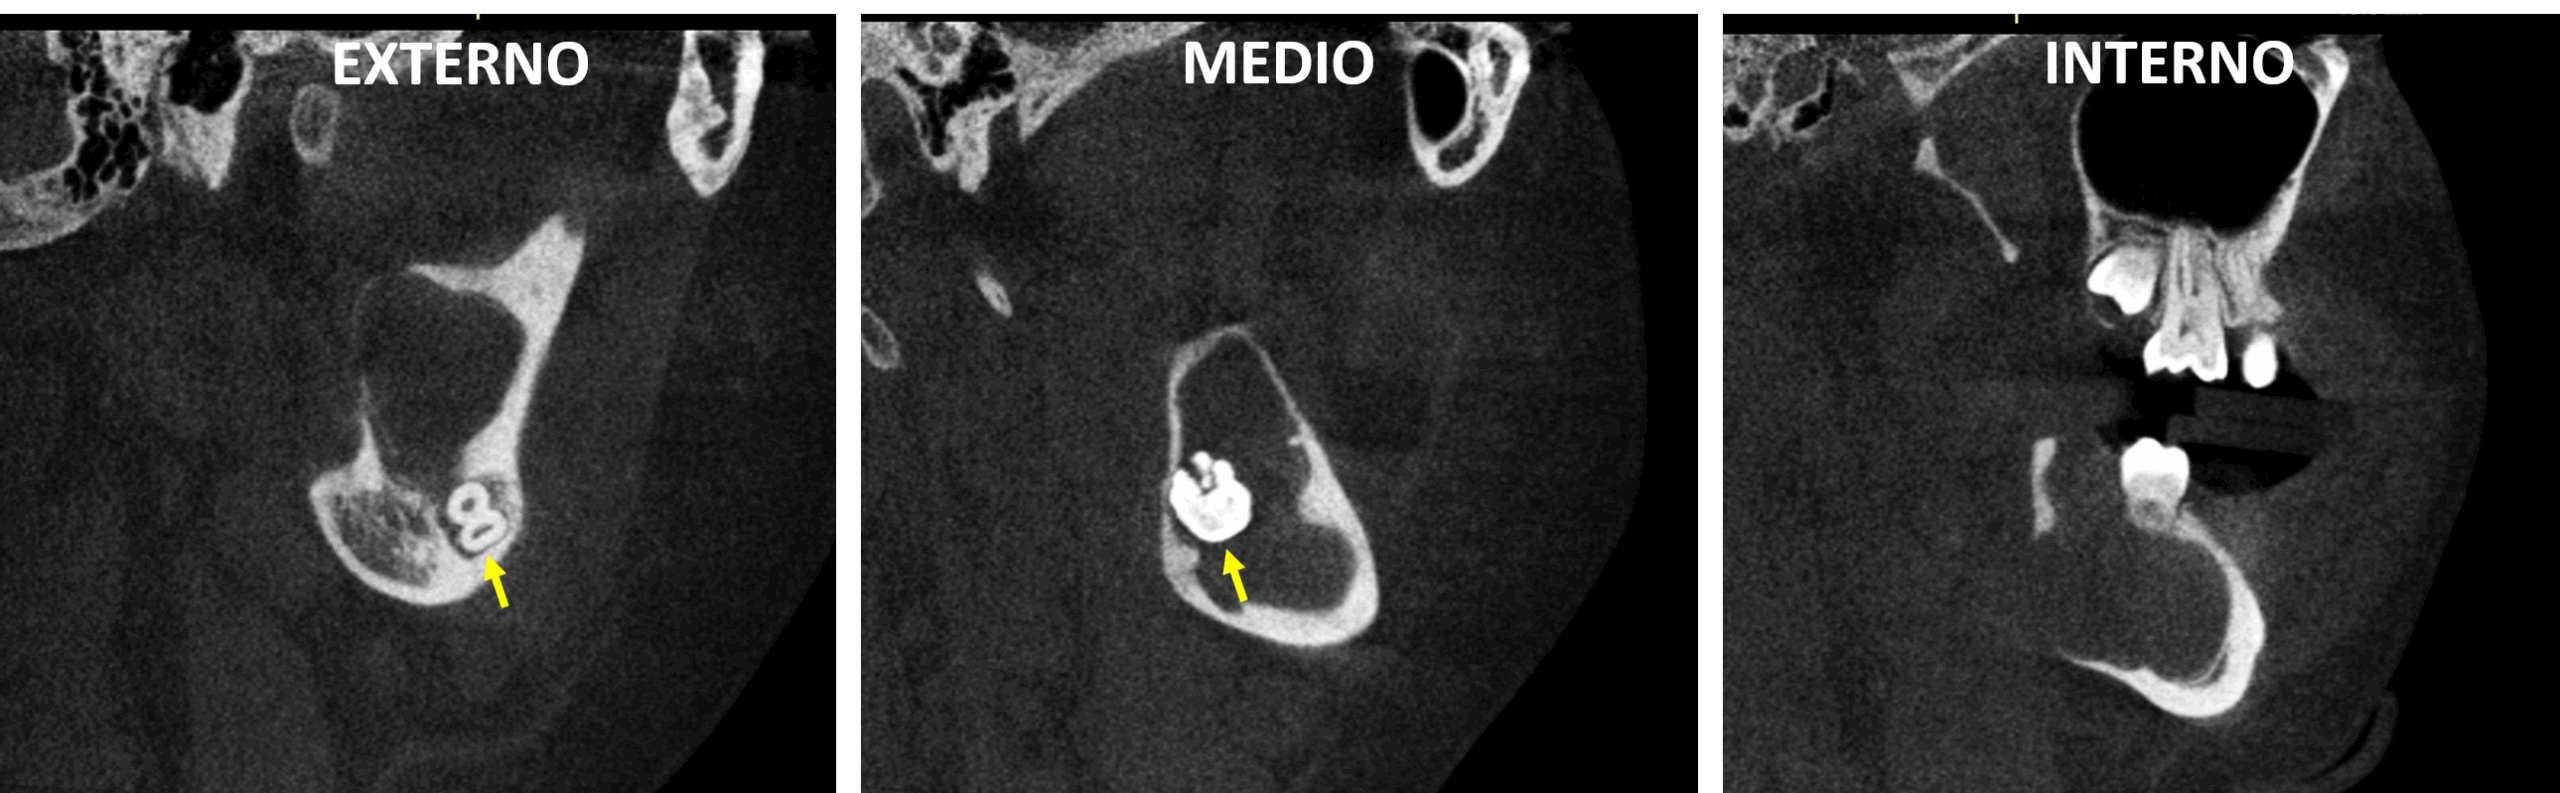

Fig.2

En cortes sagitales (Fig.2) y cortes se observa el órgano dentario 48 en aparente posición transversal con las raíces (en formación) orientadas hacia la tabla externa de la rama mandibular y la corona orientada hacia la tabla ósea interna. Asi mismo, se observa el marcado adelgazamiento de la cortical interna de la mandíbula, en los cortes axiales (Fig.3. Flechas rojas) a nivel de la rama ascendente y el cuerpo mandibular.